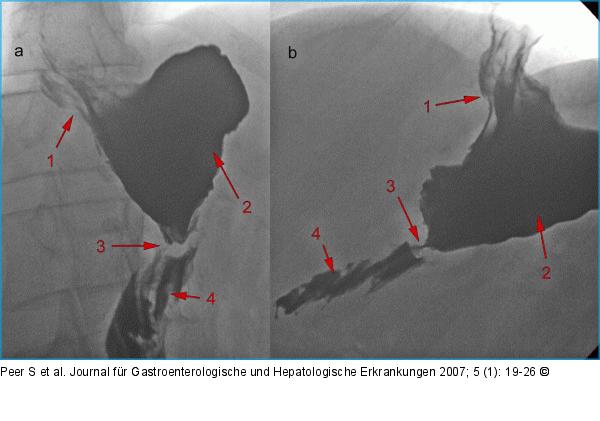

Abbildung 15: Roux-Y-Magenbypass |